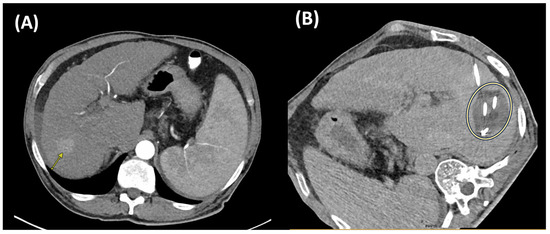

Case Report

Highlighting the Importance of Signaling Pathways and Immunohistochemistry Features in HCC: A Case Report and Literature Review

by Madalin Alexandru Hasan, Ioana Larisa Paul, Simona Cavalu, Ovidiu Laurean Pop, Lorena Paduraru, Ioan Magyar and Mihaela Doina Chirila

Reports 2025, 8(4), 197; https://doi.org/10.3390/reports8040197 - 3 Oct 2025

Background and Clinical Significance: In hepatocellular carcinoma (HCC), numerous signaling pathways become aberrantly regulated, resulting in sustained cellular proliferation and enhanced metastatic potential. Tumors that lack PYGO2 may not show the same types of tissue remodeling or regenerative features driven by the Wnt/β-catenin [...] Read more.

Background and Clinical Significance: In hepatocellular carcinoma (HCC), numerous signaling pathways become aberrantly regulated, resulting in sustained cellular proliferation and enhanced metastatic potential. Tumors that lack PYGO2 may not show the same types of tissue remodeling or regenerative features driven by the Wnt/β-catenin pathway, which could make the tumor behave differently from others that are Wnt-positive. PIK3CA-positive tumors are often associated with worse prognosis due to the aggressive nature of the PI3K/AKT pathway activation. This is linked to higher chances of metastasis, recurrence, and resistance to therapies that do not target this pathway. Case presentation: In this paper we present a rare case of hepatocellular carcinoma with PIK3CA-positive and PYGO2-negative signaling pathways, several key aspects of the tumor’s behavior, prognosis, and treatment options. Although alpha-fetoprotein (AFP) levels were significantly elevated, the CT and MRI examination showed characteristics of malignancy, HCC with secondary hepatic lesions and associated perfusion disturbances. The case particularities and immunohistochemistry features are highlighted in the context of literature review, the PIK3CA mutation suggesting the activation of the PI3K/AKT/mTOR pathway, a critical signaling pathway involved in cell survival, proliferation, and metabolism. Conclusions: Due to the aggressive nature of PIK3CA mutations, close monitoring and consideration of immunotherapy and targeted treatments are of crucial importance. Full article